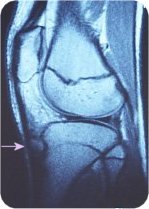

レントゲン検査が最も有用で、脛骨粗面に限局した骨端核の変化や遊離骨片を認めますが(写真2)、成長段階によって大きさは異なります。MRIはさらに有用で、骨軟骨を覆う膝蓋腱の肥厚や周囲の炎症性変化が確認できます(写真3)。超音波でも突出した骨や腱の肥厚、血管新生を確認できます。(写真4、5)

写真3 MRIの画像